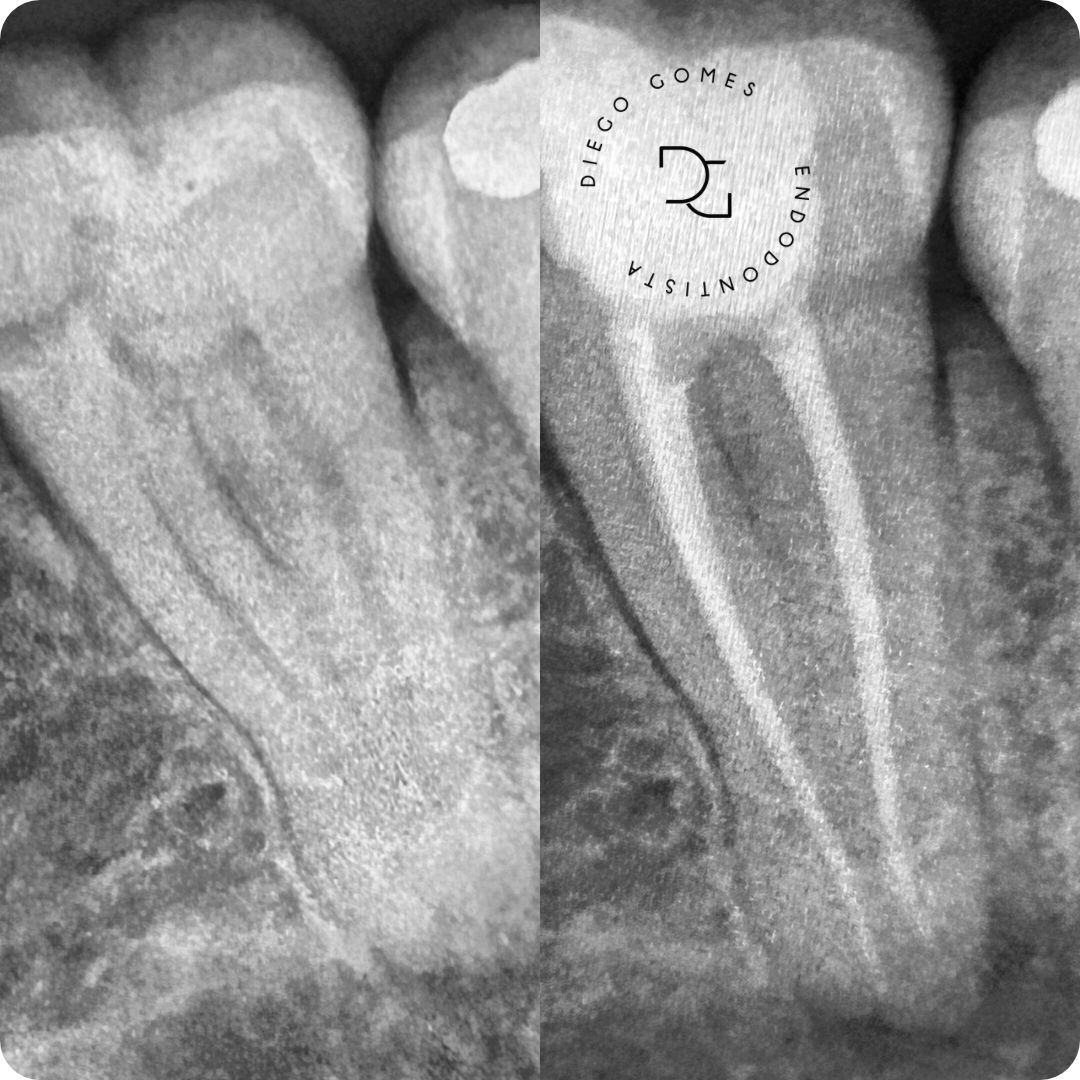

Dr. Diego Gomes é cirurgião-dentista graduado pelo centro universitário cesmac, especialista em Endodontia (ABO-Recife) e pós-graduado em Prótese Fixa, com atuação voltada para o alívio da dor, a preservação dos dentes e o cuidado integral do paciente.

Seu trabalho é baseado em diagnóstico clínico e radiográfico criterioso, uso de tecnologia e atenção individualizada. Com uma abordagem técnica precisa e humanizada, realiza o tratamento completo, incluindo procedimentos preventivos, tratamento de canal e a reabilitação do dente, permitindo que ele volte à sua função por meio de restauração em resina composta ou coroa em cerâmica e, quando necessário, pino de fibra de vidro, sempre com foco na qualidade de vida e no bem-estar.

● Tratamento e retratamento de canal

● Resolução de casos complexos